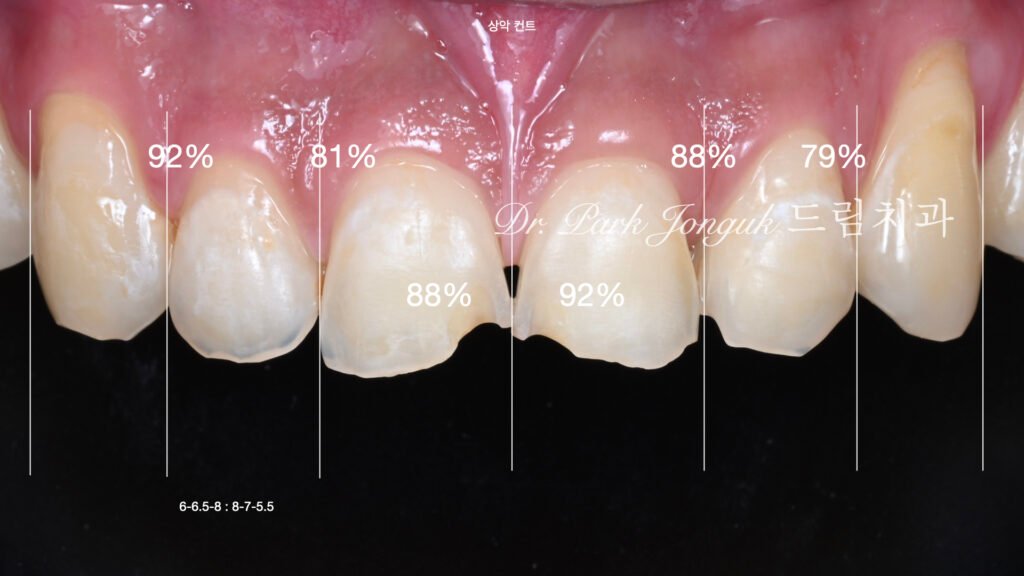

초진 평가: 심각한 구개측 부식

사진 1은 초진 시 순측(Labial) 상태입니다. 치아가 불규칙하고 깨진 것처럼 보이며, 색이 어둡고 탁합니다.

사진 2는 구개측에서 본 모습입니다. 충격적인 발견이었습니다. 구개측면까지 치아가 심하게 부식된 것을 확인할 수 있습니다. 치아 뒷면이 울퉁불퉁하고, 법랑질이 광범위하게 용해되어 있습니다.